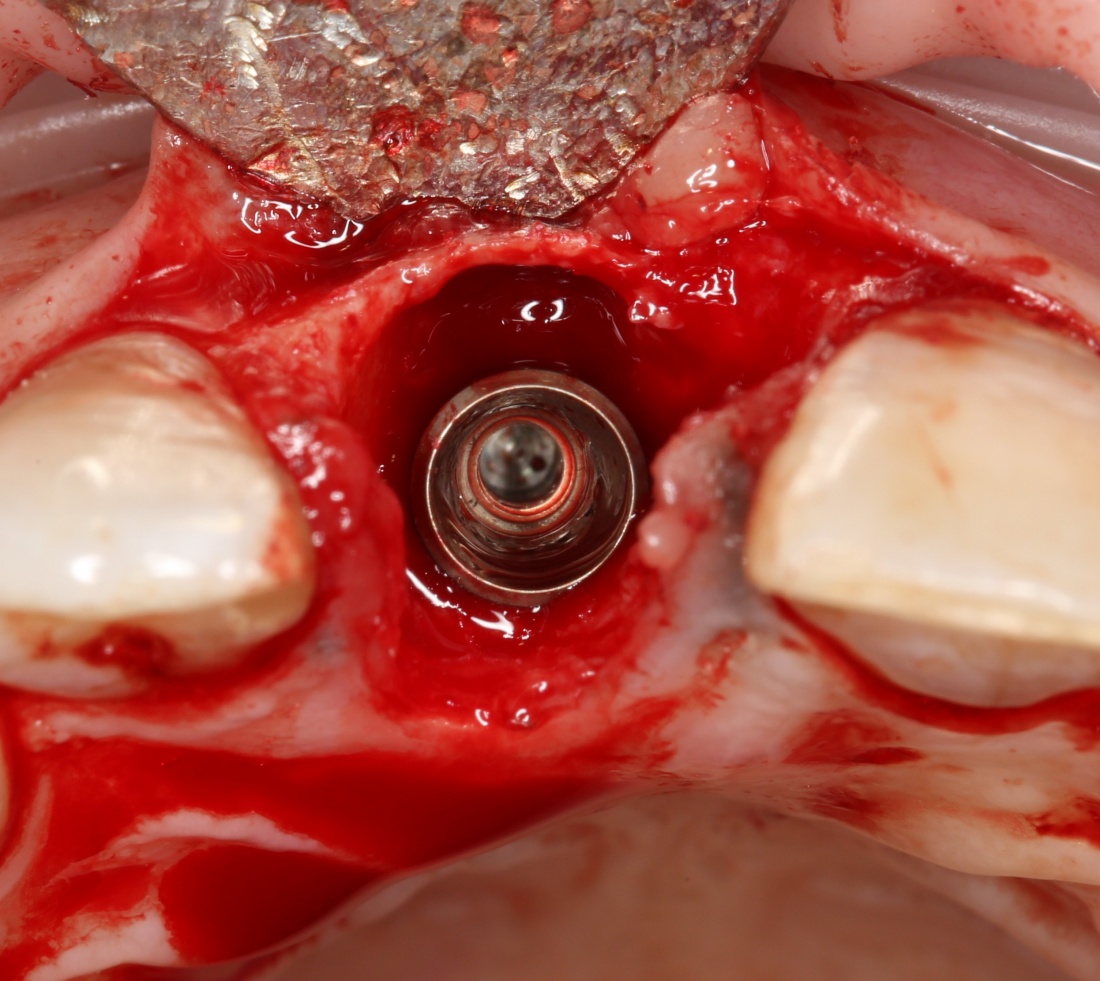

Все началось с воспаления, свищевого хода и удаления зуба:

Затем, мы готовим лунку и проверяем позиционирование импланта:

После чего аугментируем лунку. Для упаковки Bio-Oss Collagen очень удобно использовать аналоги имплантов:

Устанавливаем имплантат XiVE (Dentsply Implants):